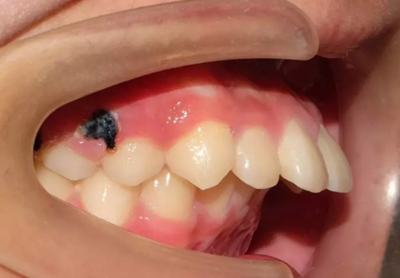

04 開合

因經(jīng)常吃不了瓜子,口腔不能執(zhí)行撕咬的動作或食物咬不斷前來就診,該如何避免?